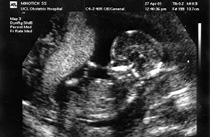

Before birth

If your doctor thinks your baby has congenital heart disease after your 20-week scan, they will ask you to have another scan. This will be with:

- an obstetrician (a doctor who specialises in care during pregnancy and childbirth)

- a specialist at a fetal (unborn baby) medicine unit

- a specialist in cardiac (heart) and child medicine.

If your baby has congenital heart disease, you will be referred to a congenital heart disease specialist who will look after you and your baby. They will be able to explain the type of congenital heart disease your baby has, and how to manage it once your baby is born.